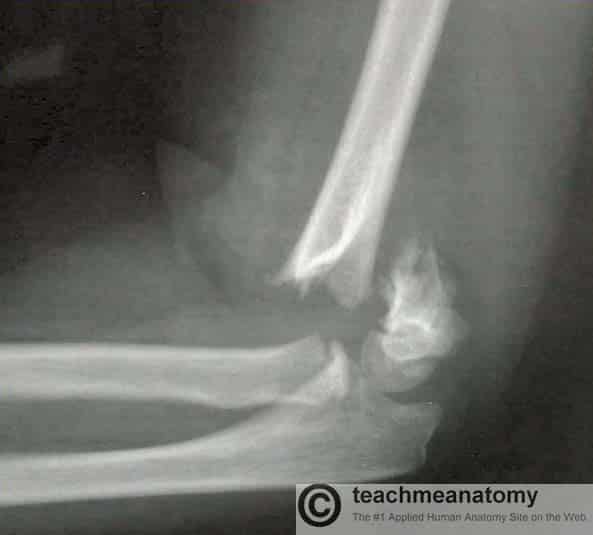

The cubital (anticubital) fossa is a triangular-shaped depression over the anterior aspect of the elbow joint. It represents an area of transition between the anatomical arm and the forearm, and conveys several important structures between these two areas. In this article, we shall look at the anatomy of the cubital fossa – its borders, contents and clinical relevance. By TeachMeSeries Ltd (2025) Fig 1The cubital fossa is a triangular-shaped depression over the anterior aspect of the elbow. Pro Feature - 3D Model You've Discovered a Pro Feature Access our 3D Model Library Explore, cut, dissect, annotate and manipulate our 3D models to visualise anatomy in a dynamic, interactive way. Learn More Borders The cubital fossa is triangular in shape and consists of three borders, a roof, and a floor: Lateral border – medial border of the brachioradialis muscle. Medial border – lateral border of the pronator teres muscle. Superior border – horizontal line drawn between the epicondyles of the humerus. Roof – bicipital aponeurosis, fascia, subcutaneous fat and skin. Floor – brachialis (proximally) and supinator (distally). By TeachMeSeries Ltd (2025) Fig 2The medial and lateral borders of the cubital fossa are formed by the muscles of the anterior forearm. Pro Feature - Dissection Images Prosection of the superficial upper limb, demonstrating the cubital fossa. The radial nerve is deep to the brachioradialis and not visible on this image. Prosection of the superficial upper limb, demonstrating the cubital fossa. The radial nerve is deep to the brachioradialis and not visible on this image. You've Discovered a Pro Feature Access our Dissection Image Library Enhance your understanding with high-resolution dissection images showcasing real-life anatomy. Learn More Contents The cubital fossa is a passageway for structures to pass between the upper arm and forearm. Its contents are (lateral to medial): Radial nerve – travels along the lateral border of the cubital fossa and divides into superficial and deep branches. It has a motor and sensory function in the posterior forearm and hand. Biceps tendon – passes centrally through the cubital fossa and attaches the radial tuberosity (immediately distal to the radial neck). It gives rise to the bicipital aponeurosis which contributes to the roof of the cubital fossa. Brachial artery – bifurcates into the radial and ulnar arteries at the apex of the cubital fossa. The brachial pulse can be felt in the cubital fossa by palpating medial to the biceps tendon Median nerve – travels medially through the cubital fossa, exiting by passing between the two heads of the pronator teres. It has a motor and sensory function in the anterior forearm and hand. The roof of the cubital fossa also contains several superficial veins. Notably, the median cubital vein, which connects the basilic and cephalic veins and can be accessed easily – a common site for venepuncture. Mnemonic for contents of the cubital fossa – Really Need (radial nerve) Beer To (biceps tendon) Be At (brachial artery) My Nicest (median nerve). By TeachMeSeries Ltd (2025) Fig 3Contents of the cubital fossa Clinical Relevance Supracondylar Fracture A supracondylar fracture is a fracture of the distal humerus. The fracture is typically transverse or oblique, and the most common mechanism of injury is falling on an outstretched hand. It is more common in children than adults. In this type of injury, the contents of the cubital fossa can be damaged – either directly, or by soft tissue swelling following the trauma. Damage to the brachial artery, if not repaired, can cause Volkmann’s ischaemic contracture (uncontrolled flexion of the hand) as the forearm flexor muscles become fibrotic and short. There also can be damage to the anterior interosseous nerve (branch of the median nerve), ulnar nerve or radial nerve. The anterior interosseous nerve can be tested by asking the patient to make an ‘OK’ sign, testing for weakness of flexor pollicis longus. The Gartland classification is used for these fractures: Type 1 is minimally displaced Type 2 is displaced with but with an intact posterior cortex Type 3 is completely off-ended. Type 1 can usually be managed conservatively with an above elbow cast whereas types 2 and 3 typically require surgical fixation with crossed, bi-cortical k-wires. By TeachMeSeries Ltd (2025) Fig 4A supracondylar fracture of the humerus Do you think you’re ready? Take the quiz below Pro Feature - Quiz The Cubital Fossa Question 1 of 3 Submitting... Skip Next Rate question: You scored 0% Skipped: 0/3 1800 More Questions Available Upgrade to TeachMeAnatomy Pro Challenge yourself with over 1800 multiple-choice questions to reinforce learning Learn More Rate This Article